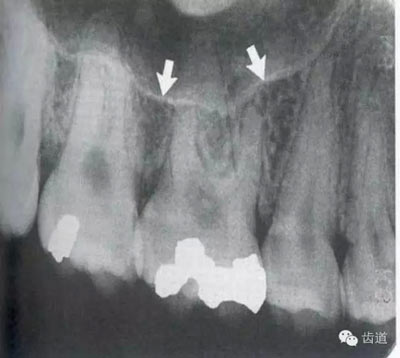

在兩個中切牙牙根之間或稍上方,多呈橢圓形密度低的影像,切牙孔影像可重疊在一側(cè)中切牙牙根尖處,易誤認(rèn)為根尖周病變,可視牙周膜和骨硬板是否完整加以鑒別

位于兩側(cè)中切牙牙根之間,由牙槽突向上,呈直線狀密度低的影像。其兩側(cè)為密度高的影像,為兩側(cè)上頜骨腭突的致密骨層。